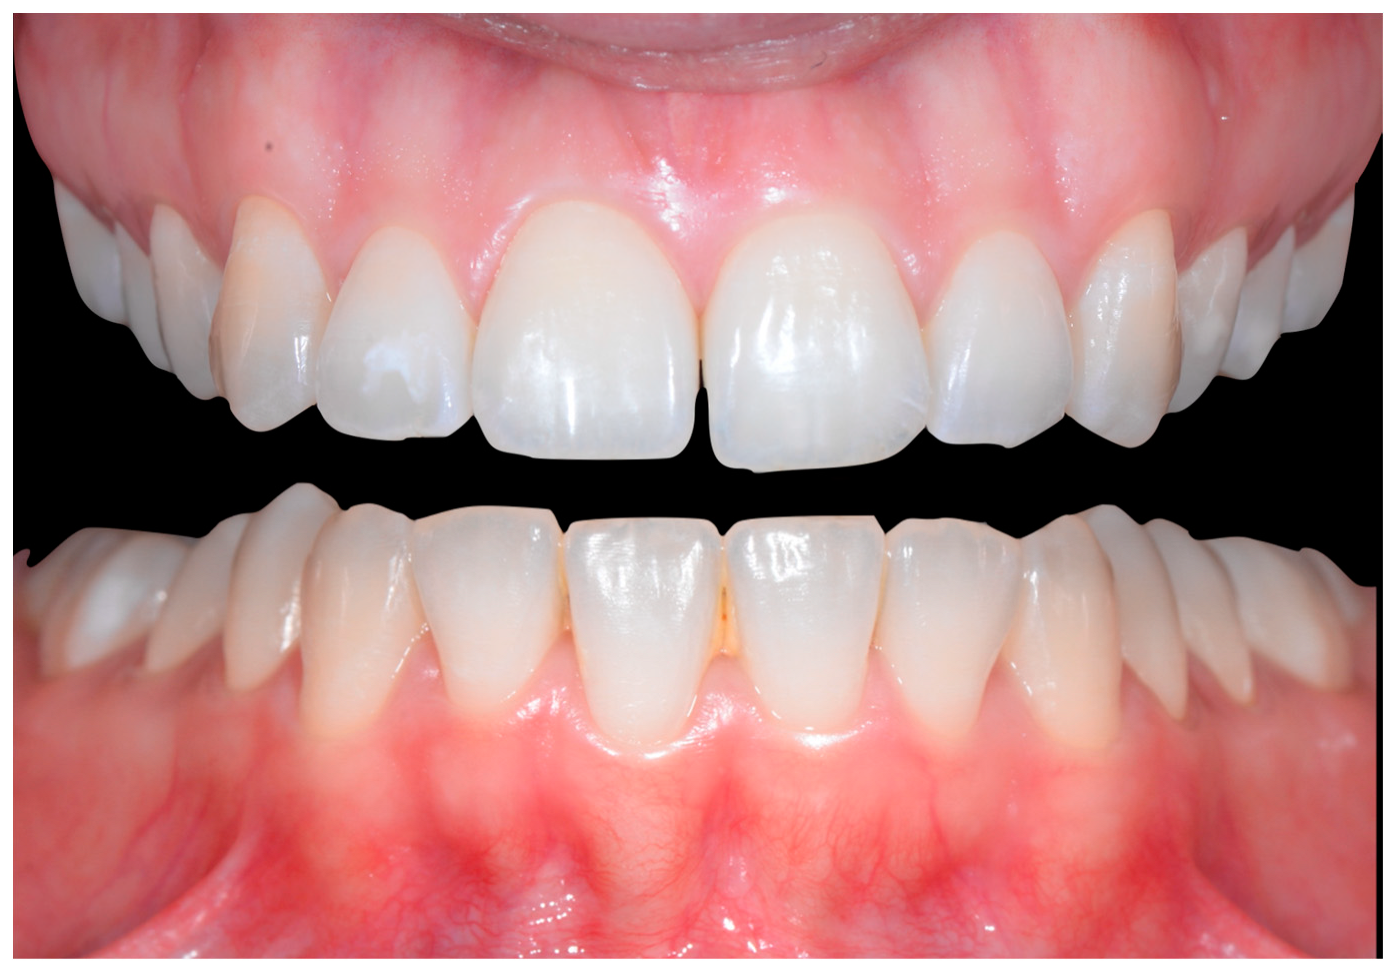

In Figure 2, the following can be observed: a difference in gingival margin height between 41 and 31, a difference in height of the incisal edges of 41 compared to the adjacent teeth, and the onset of gingival recession on 41 associated with the visibility of a vestibular arch corresponding to its root.

Early wire syndrome. Frontal views.

In Figure 6, 11 and 21 show a difference in incisal edge height and gingival margin. Tooth 41 shows gingival recession to the muco-gingival junction (Cairo’s RT1) with root visibility. Tooth 33 had a significant lingual tilt (coronal–lingual torque), not symmetrical to tooth 43.

Intermediate wire syndrome. Frontal view.